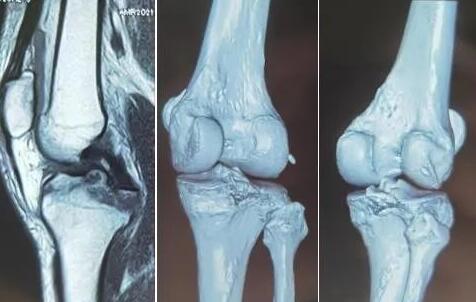

术前MRI及CT

对于后交叉韧带胫骨止点撕脱骨折的手术方式,一般分为两大类别,一类是关节镜下固定,一类是切开复位内固定。虽然两种方式各有优缺点,但综合考虑骨折程度、骨折块的大小、是否存在复合损伤及术者的技术等因素,经与患者及家属沟通,最终手术选择关节镜下固定,同时使用“天玑骨科机器人”这个好帮手辅助手术。

手术开始,术中3D-C臂扫描采集数据,三维重建骨折位置及形态,天玑骨科机器人规划骨隧道位置,自动完成进针导向器定位。主刀医生张主任沿导向器打入导针,关节镜下再次验证导针位置满意,建立骨隧道,非可吸收线“R”形捆扎后交叉韧带止点部,复位骨折端。后交叉韧带位置,走形,张力均满意。